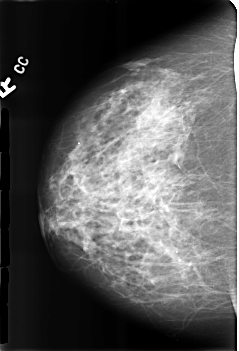

B_3174_1.RIGHT_CC

RIGHT_CC LINES 4560 PIXELS_PER_LINE 3104 BITS_PER_PIXEL 12 RESOLUTION 50 NON_OVERLAY